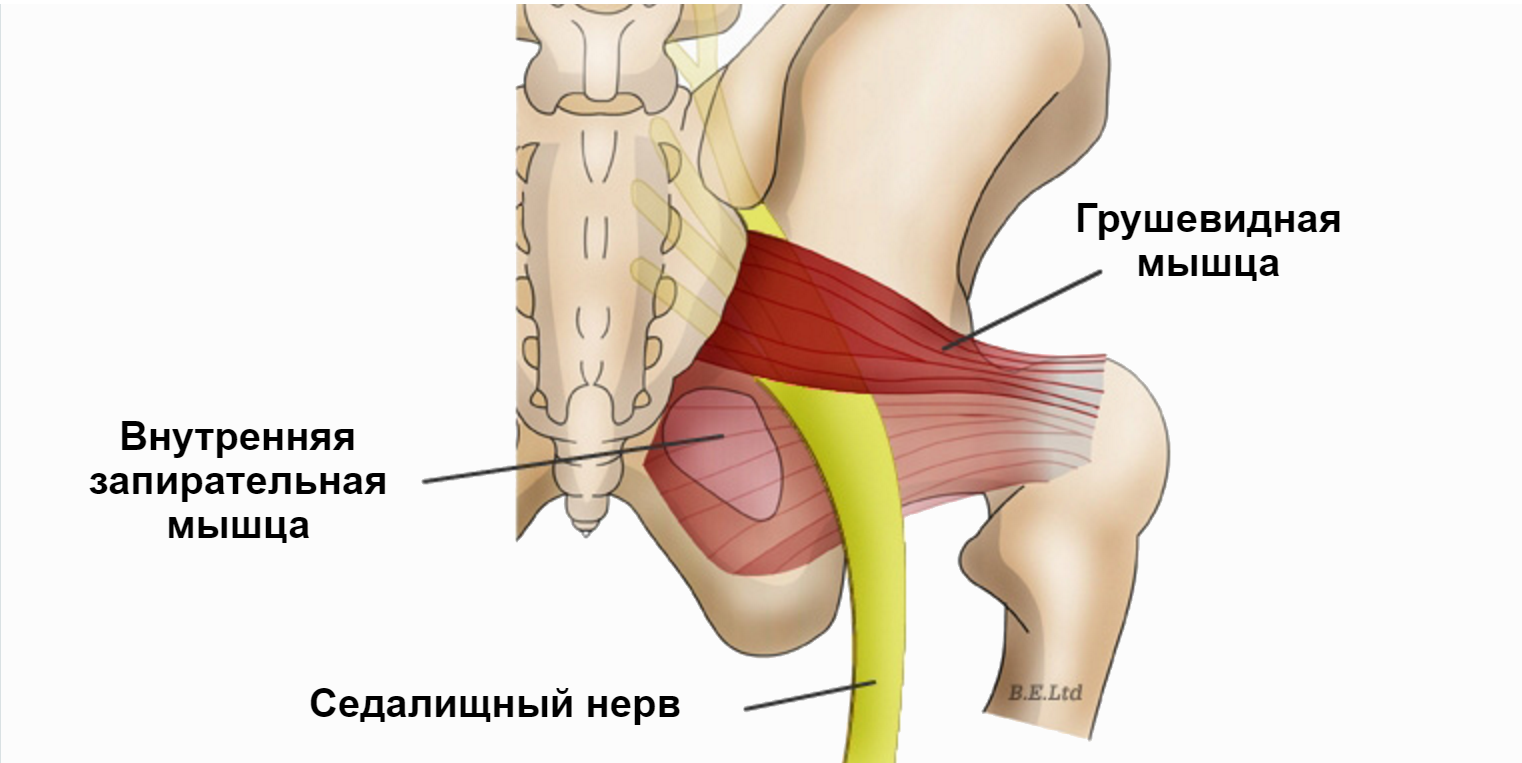

Анатомия мышц: Пириформис